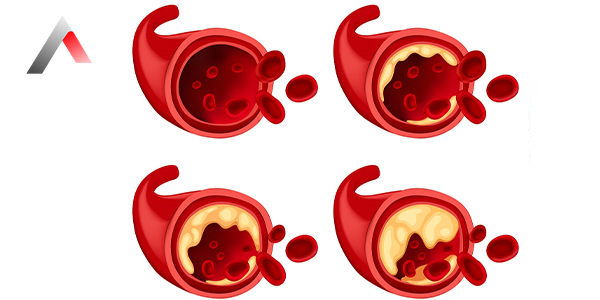

Beyin Damar Tıkanıklığı Neden Olur?

Beyin damar tıkanıklığına yol açan başlıca nedenler şunlardır:

• Ateroskleroz (damar sertleşmesi): Damarların iç duvarlarında plak birikmesi sonucu damarlar daralır ve sertleşir. Bu plak zamanla kopabilir ve beyne giden bir damarı tıkayabilir.

• Kan pıhtısı: Kalp veya boyundaki damarlarda oluşan kan pıhtıları, kan akımıyla beyne taşınabilir ve bir damarı tıkayabilir. Atriyal fibrilasyon (kalp ritim bozukluğu) gibi bazı kalp hastalıkları, kan pıhtılaşması riskini artırabilir.

• Emboli: Vücudun başka bir yerinde oluşan pıhtı veya yabancı maddeler (hava kabarcığı, yağ damlası gibi) kan dolaşımıyla beyne taşınıp damarları tıkayabilir.